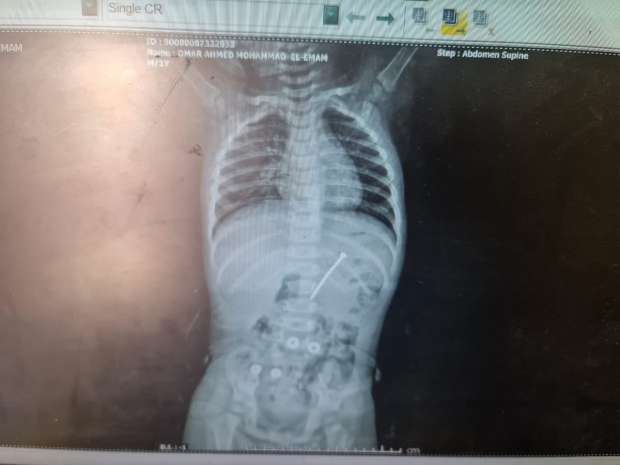

نجح قسم جراحة الأطفال بمستشفى الأطفال التخصصي في بنها، في استخراج مسمار دباسة كراسة اخترق جدار بطن طفل واستقر داخل التجويف البطني، بعد تدخّل جراحي متقدّم جمع بين المنظار وجهاز السي أرم لتحديد الموقع بدقة متناهية.

وصل الطفل إلى مستشفى الأطفال التخصصي في بنها وهو يعاني ألمًا شديدًا وقلقًا أسرته، حيث كشفت الفحوصات الأولية وجود جسم غريب حاد داخل البطن؛ إذ قرر الفريق الطبي باتخاذ الإجراءات اللازمة والحاسمة، وهو «استئصال المسمار» بأسرع وأمن بطريقة ممكنة؛ لتفادي أي مضاعفات قد تهدد حياة المريض.

وقاد الفريق الطبي بمستشفى الأطفال التخصصي في بنها، العملية بامتياز تحت إشراف الدكتور محمد متولي، رئيس قسم جراحة الأطفال، ووليد محمد، استشاري جراحة، ومحمود ممدوح، نائب قسم الجراحة، حيث تم توظيف المنظار الجراحي؛ لتقليل آثار الجراحة والشفاء السريع، فيما لعب جهاز الـ«سي أرم» دور الخريطة الحية لتحديد موقع المسمار بدقة مدهشة، ما حول العملية إلى مزيج من مهارة الجراح وذكاء الأجهزة.